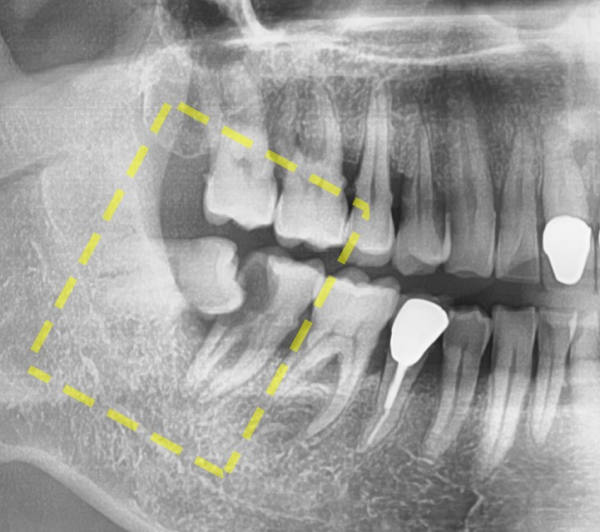

이 환자분은 어금니쪽에 통증이 있다고 하셔서

수진동치과 더서울치과를 찾아오셨습니다.

정확히 진단을 하기 위하여 엑스레이로 확인을 했는데요.

사랑니가 이렇게 누워있었습니다.

조금더 확대한 사진을 보면 누워있는 사랑니와

바로 앞에 인접한 어금니 사이에 충치가 생겨서 상당히 통증이 느껴질법한 상태였습니다.

이 환자분의 어금니 충치는 심각한 상태였기 때문에 결국 발치 후 임플란트를 하게되었습니다.

환자분의 입장에서는 사랑니때문에 치과를 찾았는데

임플란트까지 해야 한다고 하여 당황스러우실 수 있는 상황이었습니다.